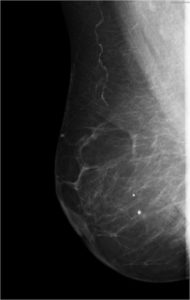

52 year old lady who underwent wide local excision for stage I breast carcinoma of right breast 7 years ago has presented for routine screening mammogram.

Ductal Cell carcinoma In Situ-DCIS RIGHT BREAST.(Comedo and cribriform type)

Craniocaudal and mediolateral oblique views of both the breast.Post operative scar is seen in the upper and outer quadrant of right breast.Pleomorphic calcifications,predominantly showing fine linear branching pattern( comedo pattern) is seen in segmental distribution with nipple convergence in the central right breast.